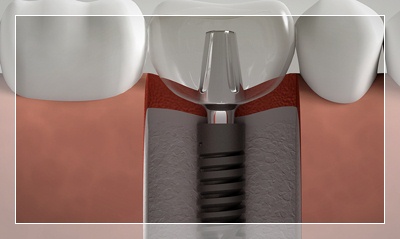

Çekim sonrası ne zaman implant yapılabilir?

Standart çekim sonrası 3-4 ay beklenir, kemik iyileşmesi sonrası implant yerleştirilir. Ancak hemen (immediate) implant tekniği ile bazı vakalarda çekim ile aynı seansta implant yapılabilir. Diş hekiminiz kemik durumuna göre en uygun zamanı belirleyecektir.

İmplantoloji

Eksik dişleriniz için en modern ve kalıcı çözüm. Titanyum implantlarla doğal diş görünümü ve fonksiyonu. Çekmeköy'de deneyimli kadromuzla implant tedavisi.